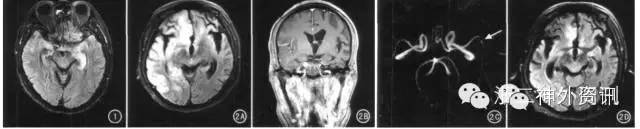

图7. 梅毒脑病:1中T2FLAIR显示左侧海马及颞叶肿胀,呈高信号,右侧海马萎缩;2A中横断面T2 FLAIR示右侧脑内额、颞、枕叶不均匀高信号,脑回肿胀;双侧半球不对称性脑萎缩;2B中右侧额颞叶脑膜增厚强化,病变区域脑组织未见强化;2C中左侧大脑中动脉局部重度狭窄;2D中为青霉素治疗32天后,右大脑半球脑炎病灶吸收,相应脑区脑萎缩加重。(自:文献[3])